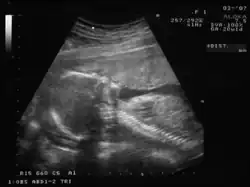

En cualquier momento del embarazo, en especial en presencia de un feto maduro en la segunda mitad del embarazo, es posible demostrar por ecografía transabdominal bidimensional o tridimensional tanto sus partes anatómicas como el saco vitelino.

Ecografía de 7 semanas -

Ecografía de 12 semanas -

Ecografía de 13 semanas -

Ecografía de 17 semanas -

Ecografía de 20 semanas